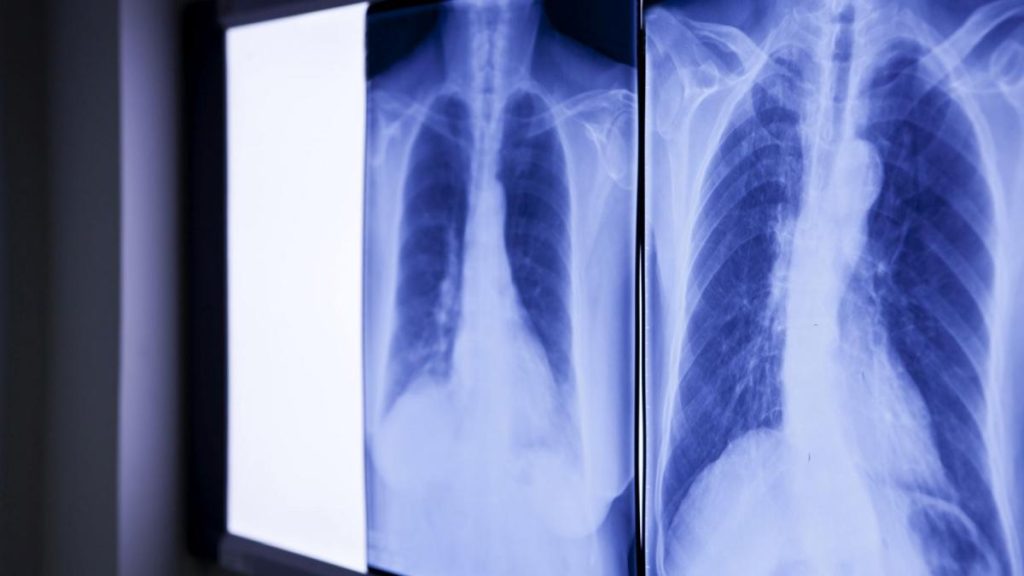

Bărbatul, identificat drept Wang, s-a prezentat la unitatea medicală acuzând dureri abdominale. În urma investigațiilor, medicii au observat un obiect străin în duodenul pacientului. O radiografie a confirmat suspiciunile: era un termometru cu mercur. Situația era cu atât mai gravă cu cât vârful dispozitivului apăsa direct pe peretele intestinal, existând riscul de perforație și hemoragie internă.